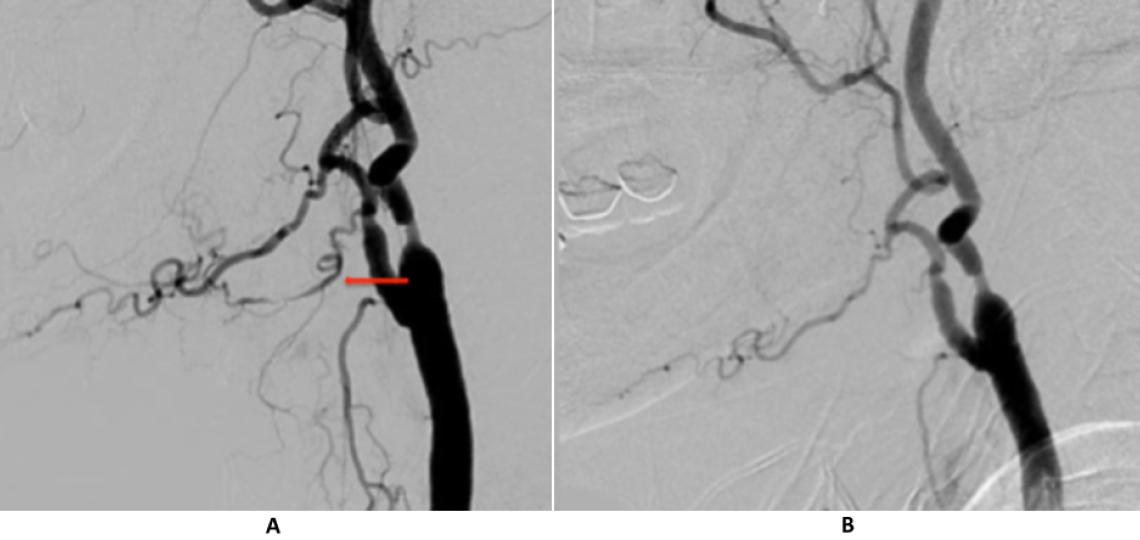

Cerebral angiogram is the most accurate way of studying blood vessels in the head and neck and provides additional information to non-invasive studies such as CT and MR angiography. During a cerebral angiogram, contrast is injected directly into the artery to outline the vessel's inside, and x-rays are taken at the same time to obtain a picture of the blood vessels. In neuro-oncology, cerebral angiography is most often used to determine the amount of narrowing in an artery or vein and the blood supply to a brain tumor. This is an invasive test, requiring the physician to insert a catheter into the femoral artery near the groin and navigate it to the arteries in the neck.

AP (A) and lateral (B) view of a right common carotid injection (normal angiogram)